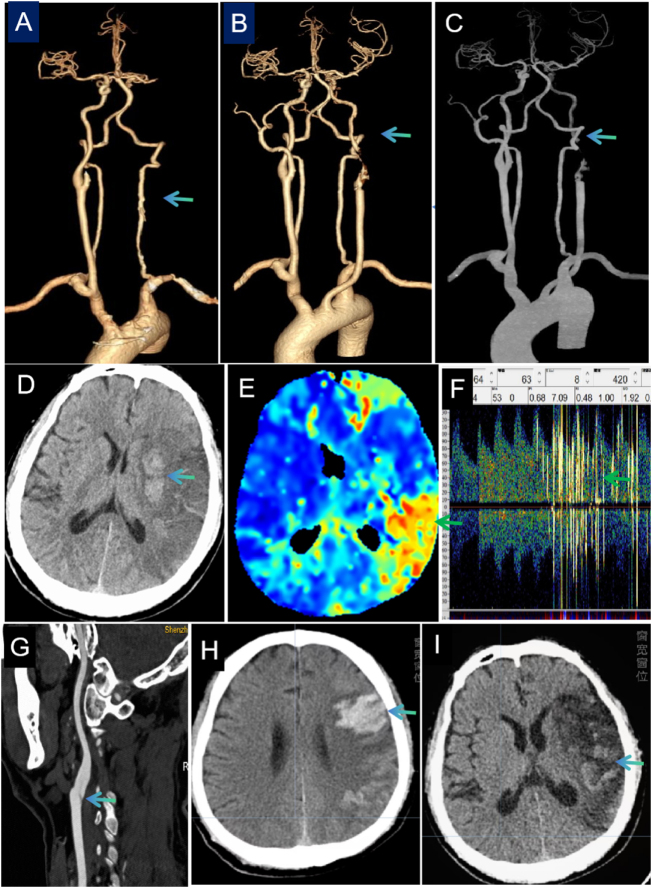

Case presentation: The patient was a 54-year-old man who presented with sudden right-sided limb weakness and speech impairment. Emergency computed tomography angiography (CTA) showed complete occlusion of the left CCA and internal carotid artery. CTA on day 1 indicated moderate-to-severe stenosis of the left CCA. Extensive low-density areas and hemorrhagic transformations were observed in the territory supplied by the left middle cerebral artery. Follow-up cranial CT on day 15 showed obvious hemorrhagic transformation following infarction. High-resolution magnetic resonance imaging of the carotid arteries on day 25 revealed no significant stenosis. The patient was given medications to improve circulation and antiplatelet aggregation, as well as lipid-lowering therapy. Follow-up cranial CT on day 37 showed significant absorption of the cerebral hemorrhage.

Clinical discussion: This case report presents a rare spontaneous recanalization of acute CCA occlusion without thrombolysis or thrombectomy. Neurological deficits resolved completely following the delayed recanalization, challenging conventional understanding of intervention timelines. The case highlights potential thrombolytic-independent recanalization mechanisms.

Conclusion: These findings raise questions about the optimal management approach in select common carotid artery occlusion cases and emphasize the importance of individualized treatment decisions based on real-time vascular imaging assessment. Early and rapid spontaneous recanalization can lead to a reperfusion injury; close monitoring and follow-up assessments are essential.